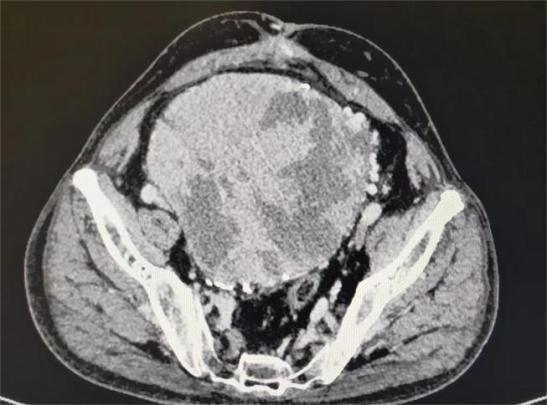

王先生住院后,医生们查阅他的各种影像资料后,均倒吸了一口凉气。王先生的肿瘤直径已达20多厘米,占据整个盆腔、周边紧压大血管和盆腔器官,手术切除犹如“虎口拔牙”,难度极大、风险极高,甚至可能引发大出血后死于手术台上。尽管王先生的家属早有心里准备,听完医生介绍病情后,看着饱受病痛折磨的父亲,家属与本人商量后,还是希望苏州大学附属第四医院的医生们能帮忙搏一搏。

术前影像学:占位范围广、周围比邻多支神经血管